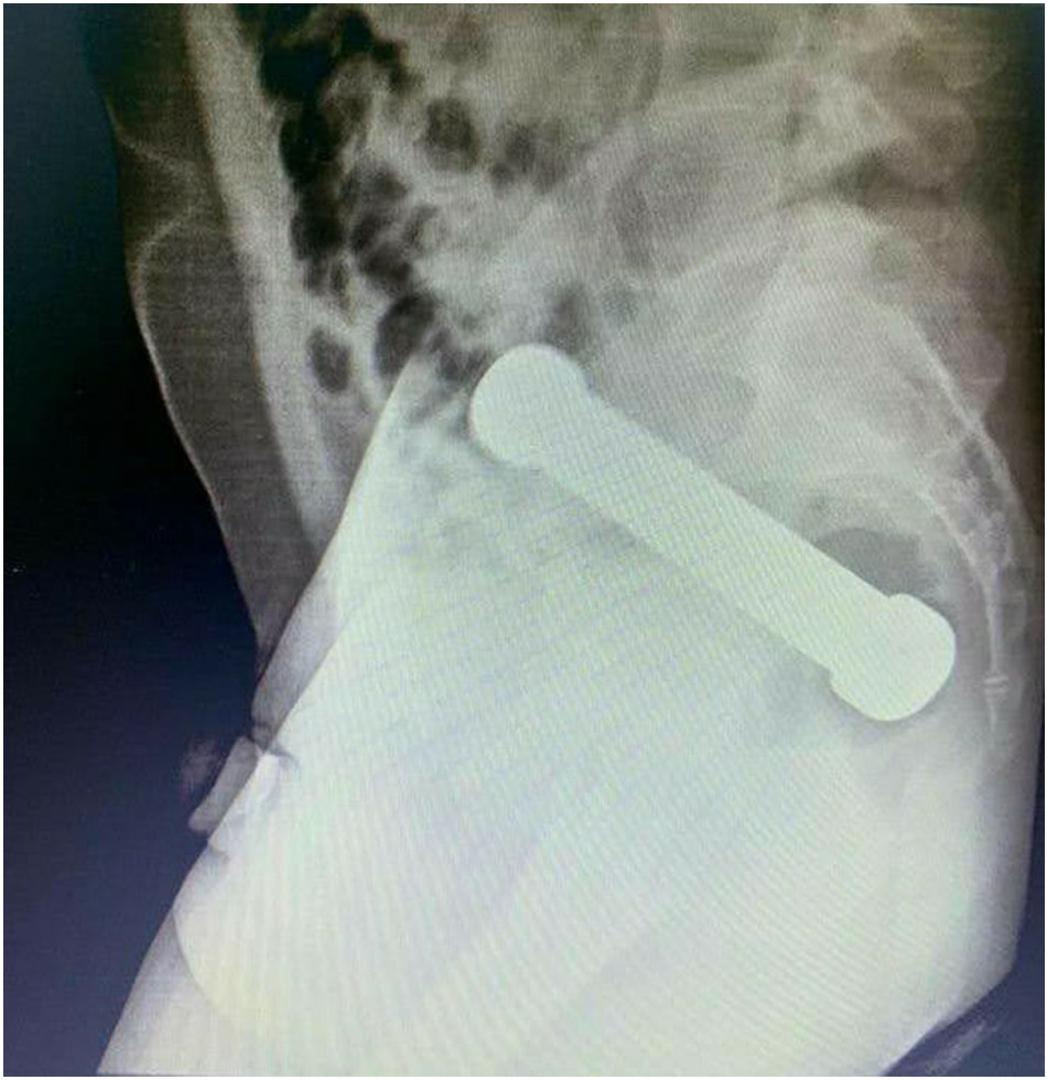

Snimka je otkrila prizor koji nitko u timu nije očekivao: metalni uteg, poznatiji kao bučica, težak čak dva kilograma i dugačak gotovo 20 centimetara, bio je zaglavljen na strateški nezgodnom mjestu - točno na prijelazu između debelog crijeva i rektuma. Veličina i oblik predmeta u potpunosti su blokirali probavni trakt, uzrokujući simptome zbog kojih je pacijent i zatražio pomoć. Liječnici su odmah shvatili da je potrebna hitna i nimalo jednostavna procedura vađenja stranog tijela kako bi se spriječile potencijalno smrtonosne komplikacije poput perforacije crijeva.